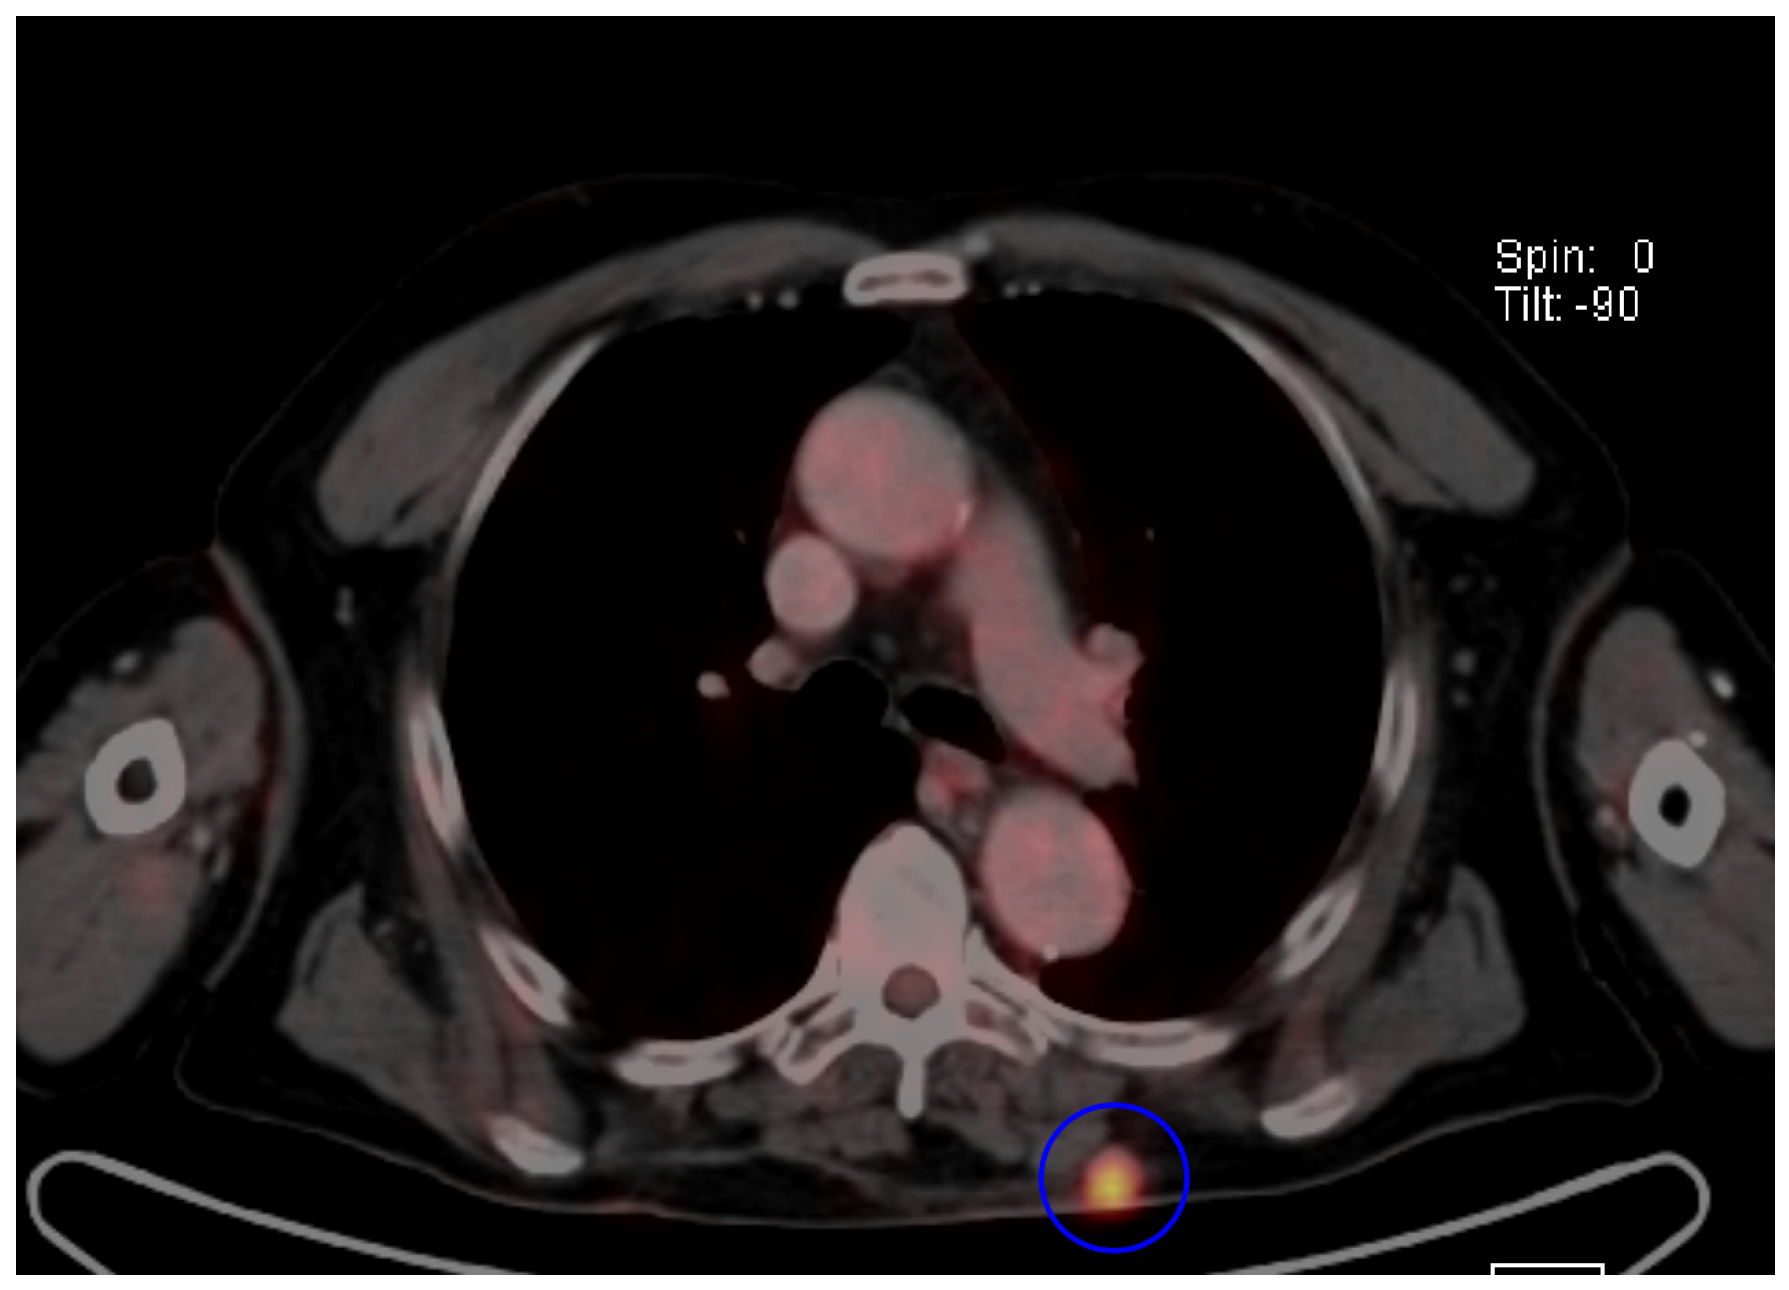

- Oh, H.Y.; Kim, D.; Choi, Y.S.; Kim, E.K.; Kim, T.E. Merkel Cell Carcinoma of the Trunk: Two Case Reports and Imaging Review. J. Korean Soc. Radiol. 2023, 84, 1134–1139. [Google Scholar] [CrossRef]